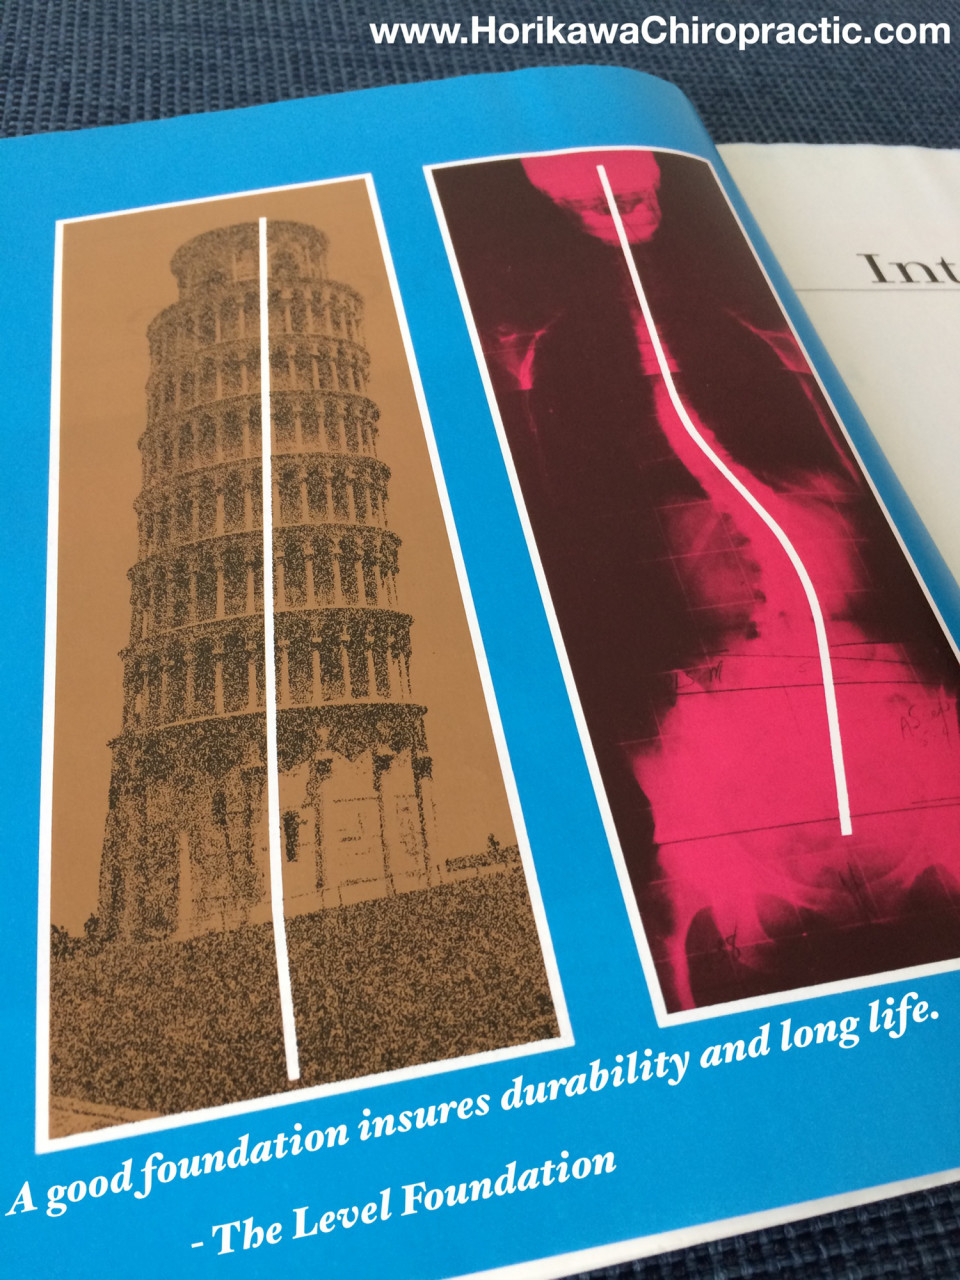

The Level Foundation

The Level Foundation

土台となる基礎の大切さ

土台となる基礎の大切さ